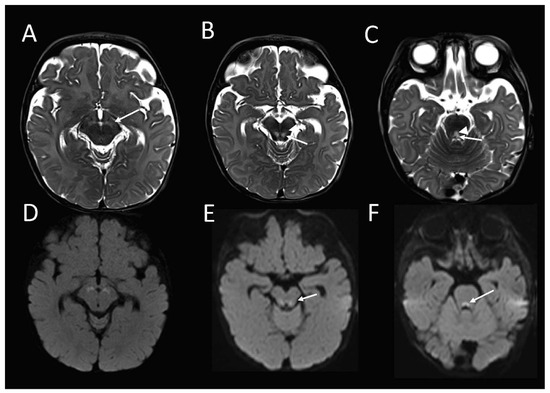

Follow up MRI performed just over 1.5 months later, demonstrated some interval signal improvement in the signal at the previously described sites. However, there were new abnormal high T2-weighted signal and associated restricted diffusion, and also developed in the red nuclei at the midbrain level (Figure 2A,E); in the CTT and ML at the mid pons level, (Figure 2B,F); in the MLF and TecSP (and possibly also ML) at the open medulla level (Figure 2C,G); and changes in the MLF and ML (i.e. the internal arcuate fibres of sensory decussation) at the upper part of the closed medulla, inferiorly (Figure 2D,H).

Figure 2. Brain MRI from the patient with compound heterozygous PYROXD2 variants at 6 months. The axial T2-weighted sequence shows the interval development of abnormally high signal in the (A) red nuclei at the midbrain level; (B) central tegmental tracts and medial lemnisci (ML) (arrow), at the level of mid pons; (C) central dorsal medulla, involving the middle longitudinal fasciculi (MLF), and the tectospinal tracts (arrow), at the open medullary level; and (D) sensory decussation of ML (arrowhead), and MLF (arrow) at the upper part of closed medulla, with corresponding restricted diffusion (EH) on diffusion-weighted imaging.